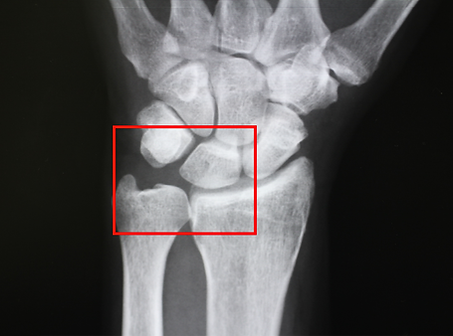

TFCC損傷の原因となる尺骨突き上げ症候群とは。

尺骨突き上げ症候群S-HANDクリニック 埼玉県さいたま市 手外科。